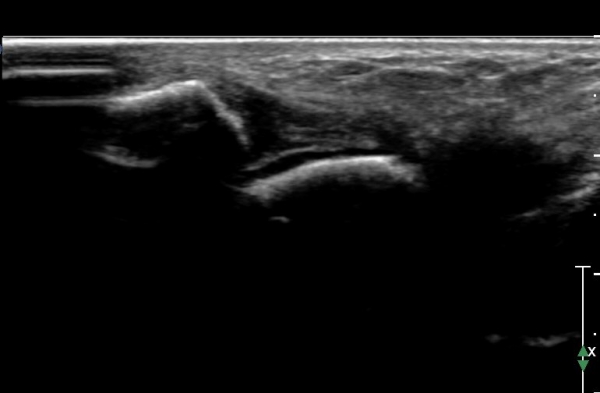

ÇϺΠ½ÅÀü ¶ì(inferior extensor retinaculum) ÀÇ frondiform Àδë Á¾´Ü¸é°Ë»ç¿¡¼­

frondiformÀδëÀÇ Àú¿¡ÄÚ ºÎÁ¾°ú °Å°ñÇÏ °üÀý °£°ÝÀÌ ¹ú¾îÁ® ÀÖ´Ù(»çÁø 8, 9).